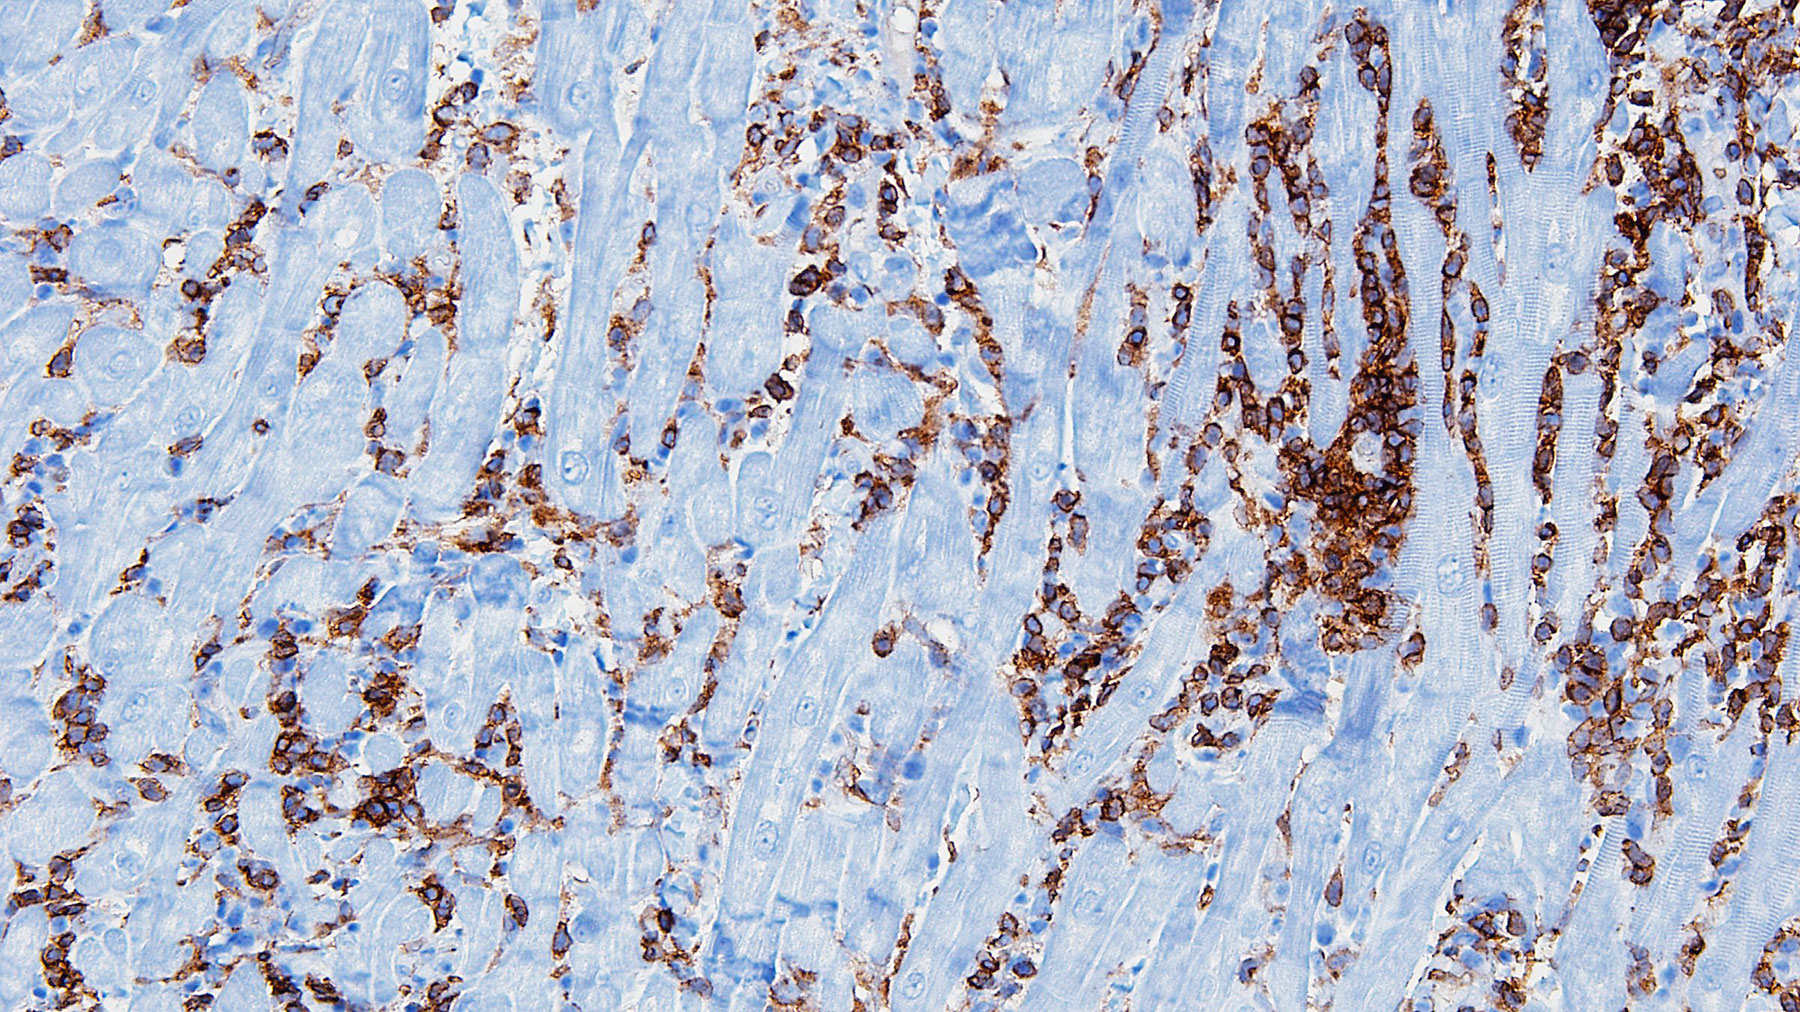

Figure G. IHC CD4 stain x20

Histology: Biopsy of the myocardial tissue performed at one month after the transplant showed myocardial tissue with diffuse and severe polymorphous mononuclear infiltrates with extensive myocyte damage, interstitial edema, vasculitis and focal necrosis (H&E staining in Figures A, C & E, and corresponding trichrome stains in Figures B, D & F). Special immunohistochemistry (IHC) stain for CD4 in a consecutive section from E and F (Figure G) shows a predominant infiltrate for helper cells.  All these features are consistent with severe acute cellular rejection, ISHLT 2004 Grade 3R (ISHLT 1990 Grade 3B).